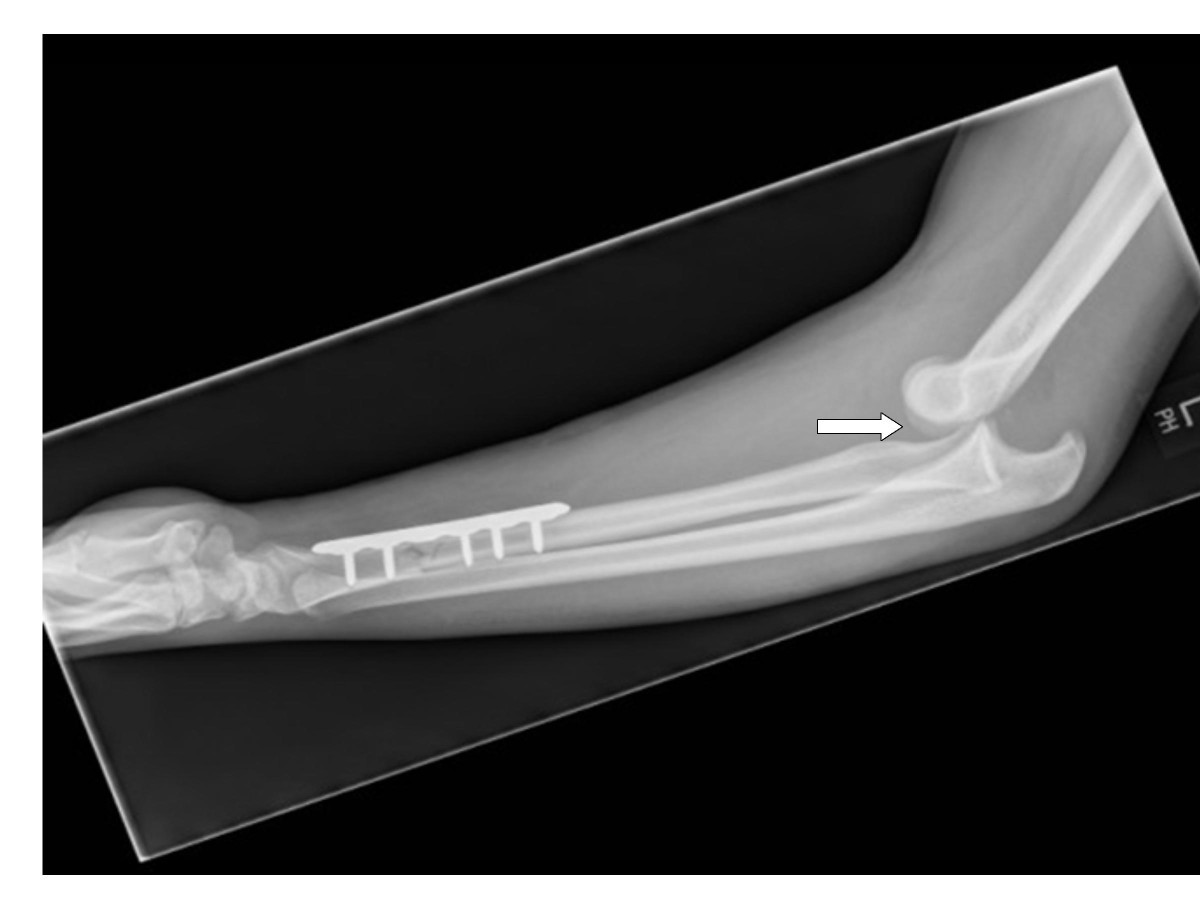

From jmedicalcasereports.biomedcentral.com

Subacute dislocation of the elbow following Galeazzi fracturedislocation of the radius A case Radius Dislocation Elbow The humerus (your upper arm bone). elbow dislocations account for 10% to 25% of elbow. Elbow dislocations can be complete or partial, and. an elbow dislocation happens when the bones of the forearm (the radius and ulna) move out of place, compared. your elbow joint is where three bones in your arm come together: elbow dislocations. Radius Dislocation Elbow.